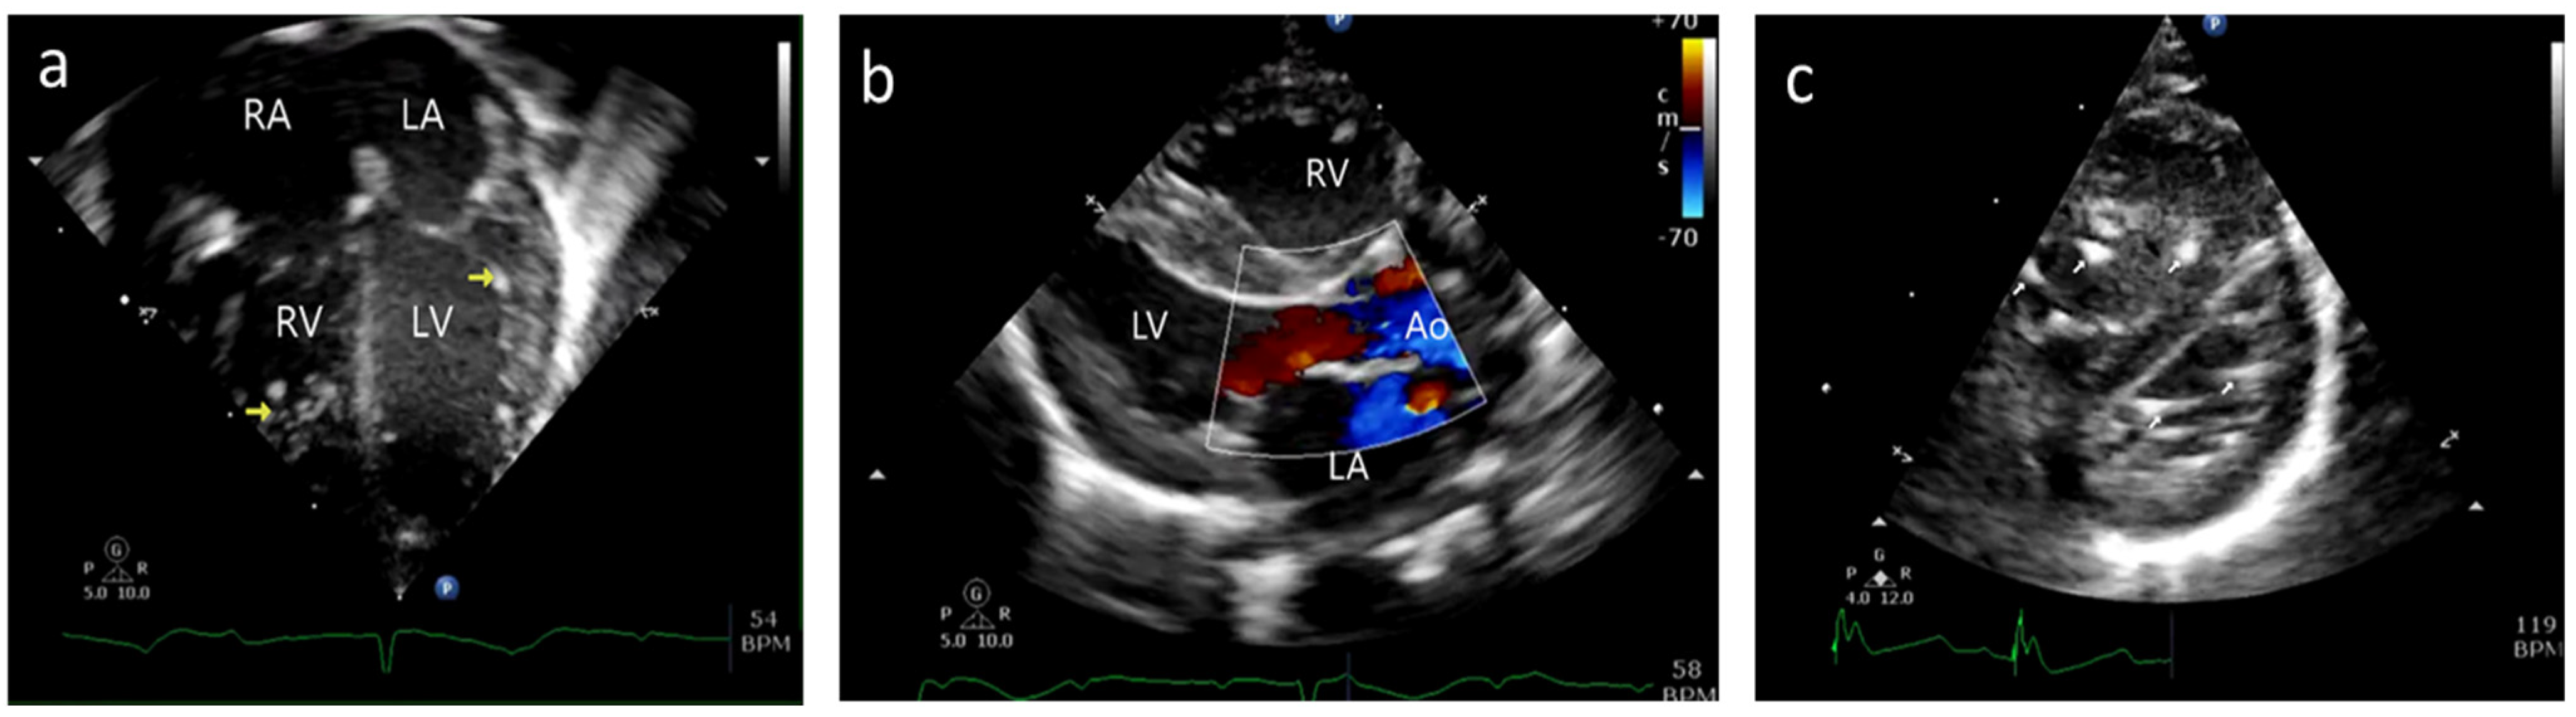

2.1.1. Case A

2.1.2. Case B

5.5. Echocardiography Correlation